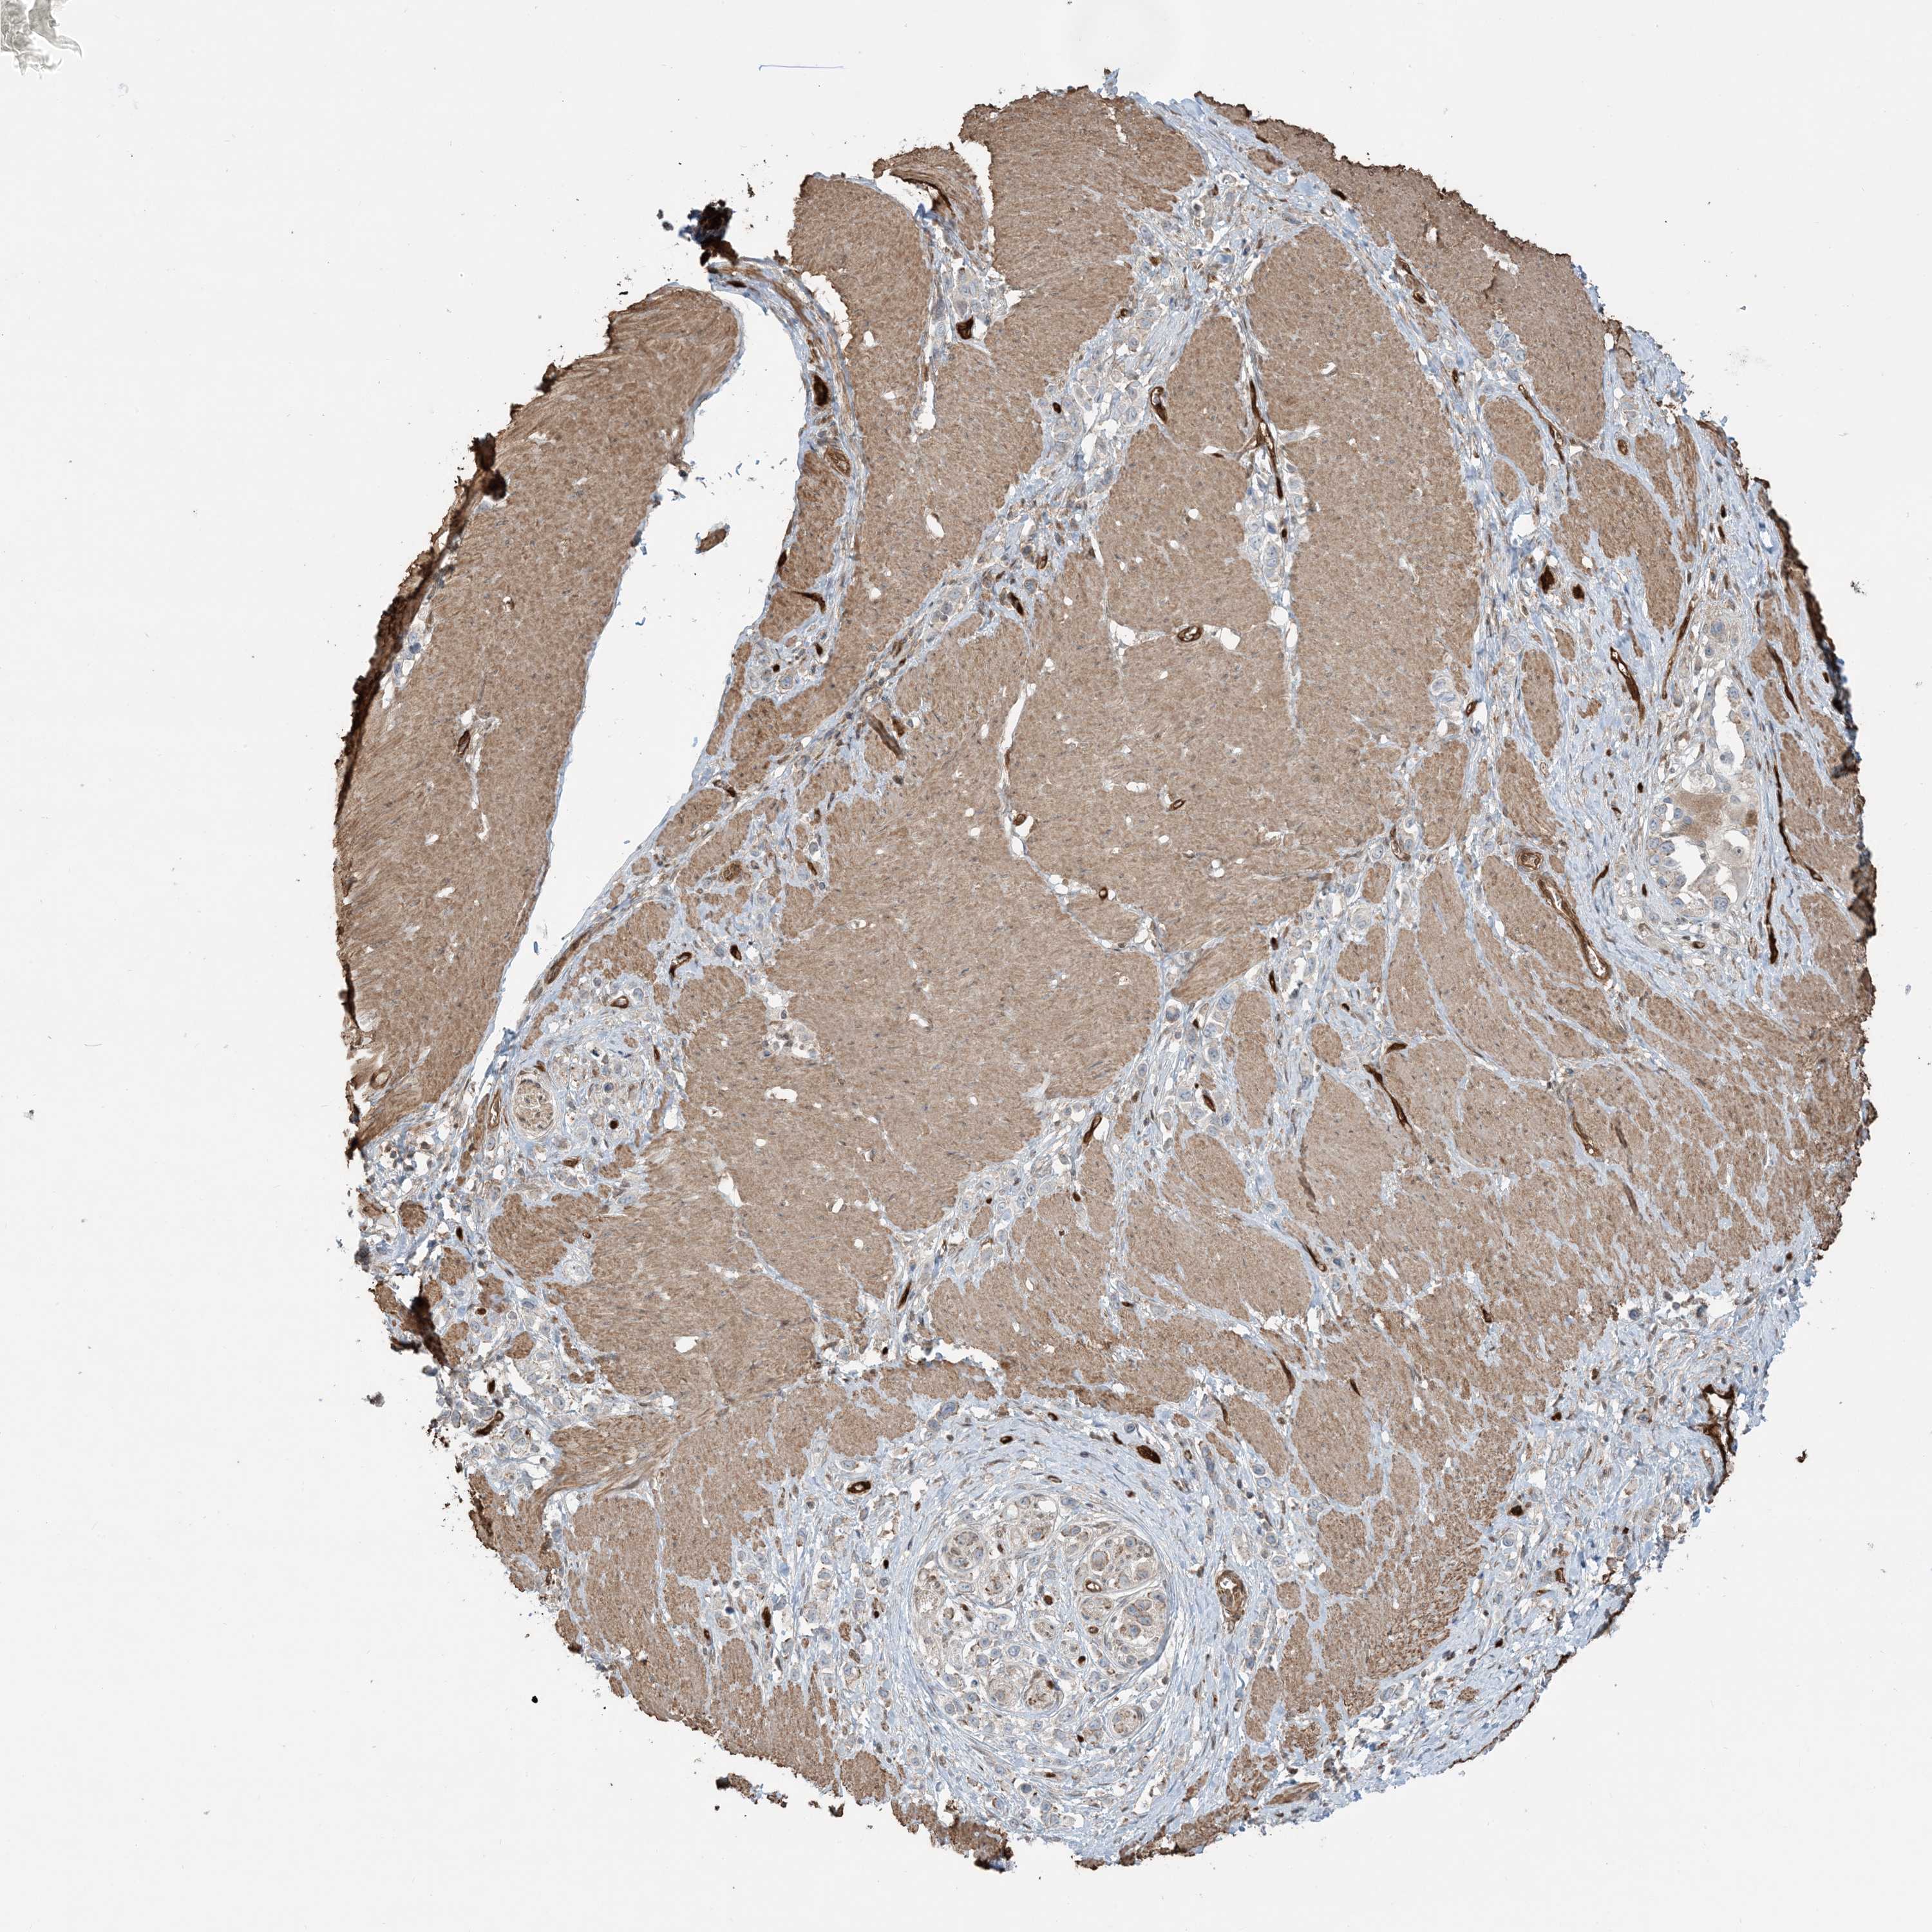

STOMACH CANCER - Protein expressioni

A mouse-over function shows sample information and annotation data. Click on an image to view it in a full screen mode. Samples can be filtered based on level of antibody staining by selecting one or several of the following categories: high, medium, low and not detected. The assay and annotation is described here.

Note that samples used for immunohistochemistry by the Human Protein Atlas do not correspond to samples in the TCGA dataset.

Antibody stainingi

Antibody staining in the annotated cell types in the current human tissue is reported as not detected, low, medium, or high, based on conventional immunohistochemistry profiling in selected tissues. This score is based on the combination of the staining intensity and fraction of stained cells.

Each image is clickable and will lead to virtual microscopy that enables deeper exploration of all samples and also displays staining intensity scores, fraction scores and subcellular localization as well as patient and tissue information for each sample.

Antibody HPA030989

Antibody HPA030990

Staining

High

Medium

Low

Not detected

Intensity

Strong

Moderate

Weak

Negative

Quantity

>75%

75%-25%

<25%

None

Location

Nuclear

Cytoplasmic/membranous

Cytoplasmic/membranous,nuclear

Adenocarcinoma, NOS